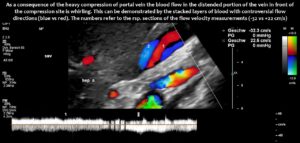

Compression of the superior mesenteric vein and its distension not only compresses the duodenum, but also reduces venous return from the small bowel, which can impair food absorption. Blocked blood flow at the compression site can be demonstrated by a whirling blood stream in front of the compression. Subsequent layers demonstrate antegrade and retrograde flow, as can be seen in the layering of blue and red flow inside the enlarged vein, pointing to changing flow directions and the different flow directions in these layers as highlighted by the spectral analyses at the bottom of the image.